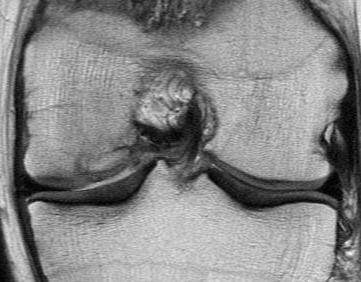

Technique Mosaicplasty Type 3 OCD

Debride base of OCD and reduce

Drill site of mosaicplasty with 4.5 mm drill

- overdrill 2 - 4 mm

- do not want to leave plug proud

- impossible to sink further or remove